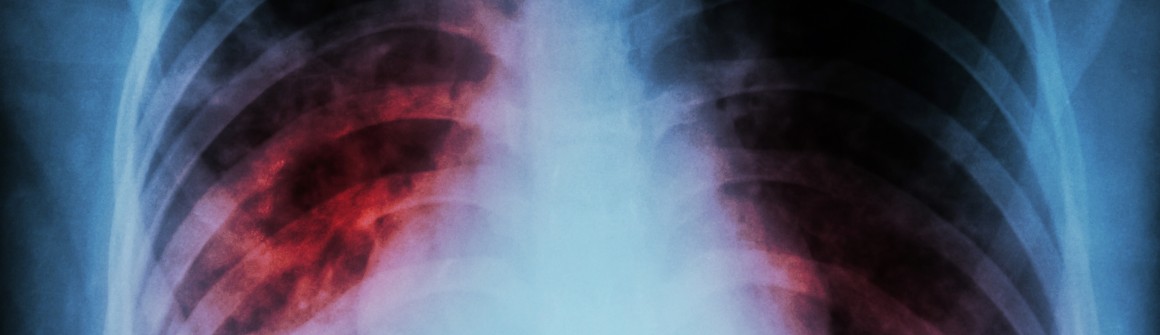

Die Tuberkuloseüberwachung ist ein integraler Bestandteil unserer Bemühungen, Tuberkulose innerhalb unserer Gemeinschaft zu kontrollieren und zu verhindern. Tuberkulose ist eine ansteckende Krankheit, die durch das Bakterium Mycobacterium tuberculosis verursacht wird und kann verschiedene Organe befallen. Obwohl Tuberkulose heilbar ist, bleibt sie eine ernste Bedrohung für die öffentliche Gesundheit.

Man unterscheidet zwischen einer offenen, also übertragbaren, und einer geschlossenen Tuberkulose. Sie müssen in der Regel über einen Zeitraum von zwei Monaten vier verschiedene Antibiotika einnehmen und dann für einen Zeitraum von ca. vier Monaten zwei verschiedene Antibiotika. Außerdem ist eine augenärztliche Vorstellung wichtig und es erfolgen außerdem routinemäßig Blutentnahmen sowie Röntgenuntersuchungen.